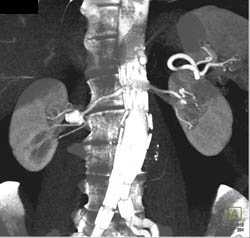

CASE NUMBER 3,554

Renal Artery Aneurysm